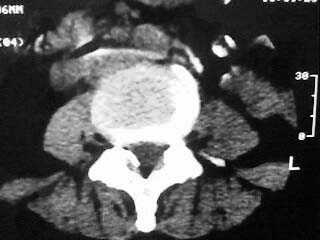

f,64。腰痛,腿麻三个月

是黄韧带钙化吗

腰椎退行性变;黄韧带钙化。

黄韧带增厚钙化

也可以是小关节增生所致.